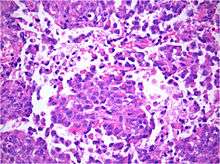

Histology

Histology is the study of the microscopic anatomy of cells and tissues of plants and animals. It is performed by examining a thin slice of tissue under a light microscope. The tumor histopathology is jumbled small and large cells. The tissue of this tumor contains many different types of cells including the rhabdoid cells, large spindled cell, epithelial and mesenchymal cells and areas resembling primitive neuroectodermal tumor (PNET). As much as 70% of the tumor may be made up of PNET-like cells. Ultrastructure characteristic whorls of intermediate filaments in the rhabdoid tumors (as with rhabdoid tumors in any area of the body). Ho and associates found sickle-shaped embracing cells, previously unreported, in all of 11 cases of AT/RT.[16]